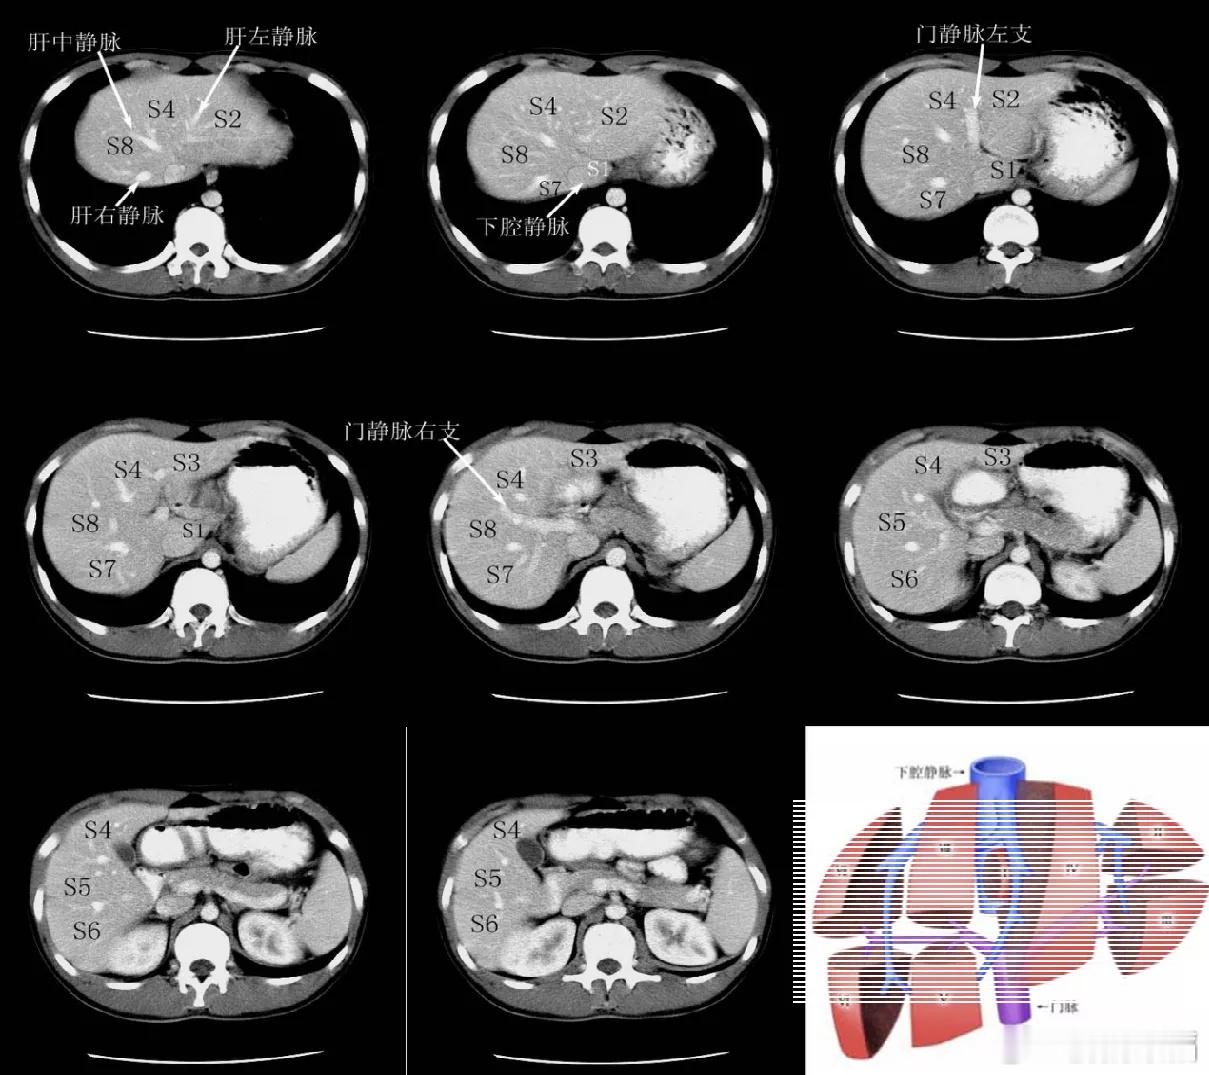

他们建议是说,因为甲胎和凝血也高了,现在这个位置还比较深,在那个切除面儿比较大。他建议就不管性质,直接进行消融,处理了就安心。为后面如果病情发展留一些空间

1\消融的主要问题是,不能确定病变性质

2\当然,如果的确外科切除位置不好弄,也只有这个方案。

他们建议是说,因为甲胎和凝血也高了,现在这个位置还比较深,在那个切除面儿比较大。他建议就不管性质,直接进行消融,处理了就安心。为后面如果病情发展留一些空间

1\消融的主要问题是,不能确定病变性质

2\当然,如果的确外科切除位置不好弄,也只有这个方案。